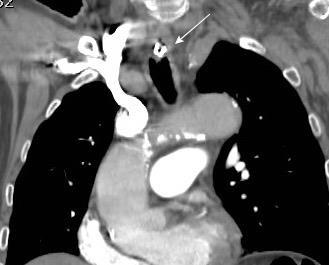

Masa axilar izquierda y derrame pleural derecho. Implantes pleurales, paraespinales . Ganglios en mamaria interna. Linfoma B difuso

Jaffe ES. Diagnosis and Classification of Lymphoma: Impact of Technical Advances.

2005. Masa pulmonar.